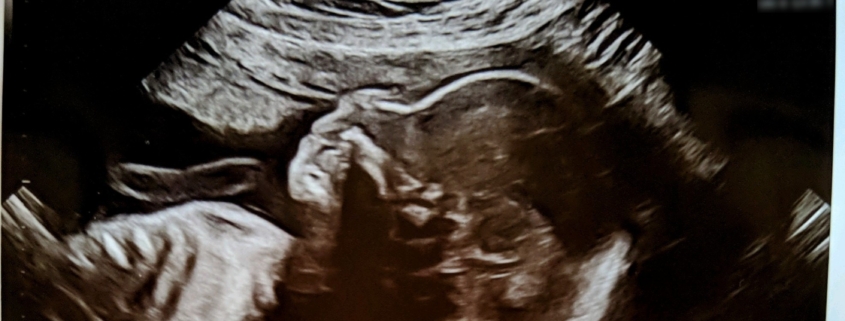

2) There’s a lot of ambiguity around the definition of “consciousness,” so it’s hard to say which fetal behavior would suggest “consciousness.” One suggestion is that once the fetus can plan actions (as opposed to acting only on reflex) this action planning indicates a level of consciousness. There is evidence of action planning anywhere from 13 weeks through 22 weeks, all before the 24 week mark of cortical connections. For example:

Fetal movements in twin gestations were studied, utilizing 4-D ultrasound from 14 weeks gestation. The study noted action planning via purposeful movements of the fetuses toward the co-twin, as well as self-directed movements. The study also noted differentiation in the velocity of targeted fetal movements. Slower velocity of fetal movements was noted toward the co-twin as well as with self-directed movements toward the sensitive eye regions, when compared to non-targeted movements toward the uterine wall, for example. The presence of such action planning, learning, and social behavior raises consideration of fetal consciousness and awareness by 14 weeks gestation.

As far as facial reactions, compared to newborns, fetuses don’t have as much adipose tissue (fat) or neuromuscular development, so in general they aren’t yet physically capable of as many different facial expressions as a newborn would be. Still, some facial movements are observable via ultrasound by 20 weeks, and research has found fetuses make certain faces more often when receiving injections for fetal surgery compared to when not. Their expressions in response to these shots are similar to the expressions of infants in response to pain.